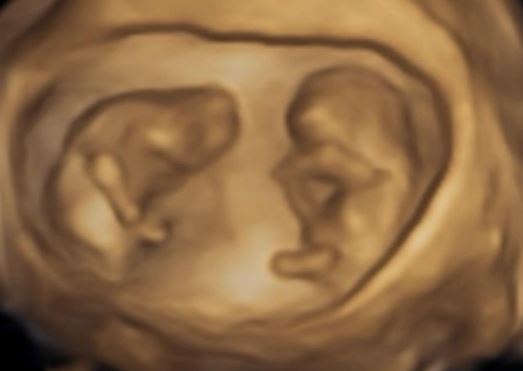

女星鄭家純(雞排妹)在2022年嫁給日籍老公Akira,婚後過得相當幸福,而先前發文才被猜測是否因為「害喜」才暈車的鄭家純,如今透過社群證實懷孕,且是同卵雙胞胎,她曬出寶寶超音波表示,2個孩子頭一上一下像太極。